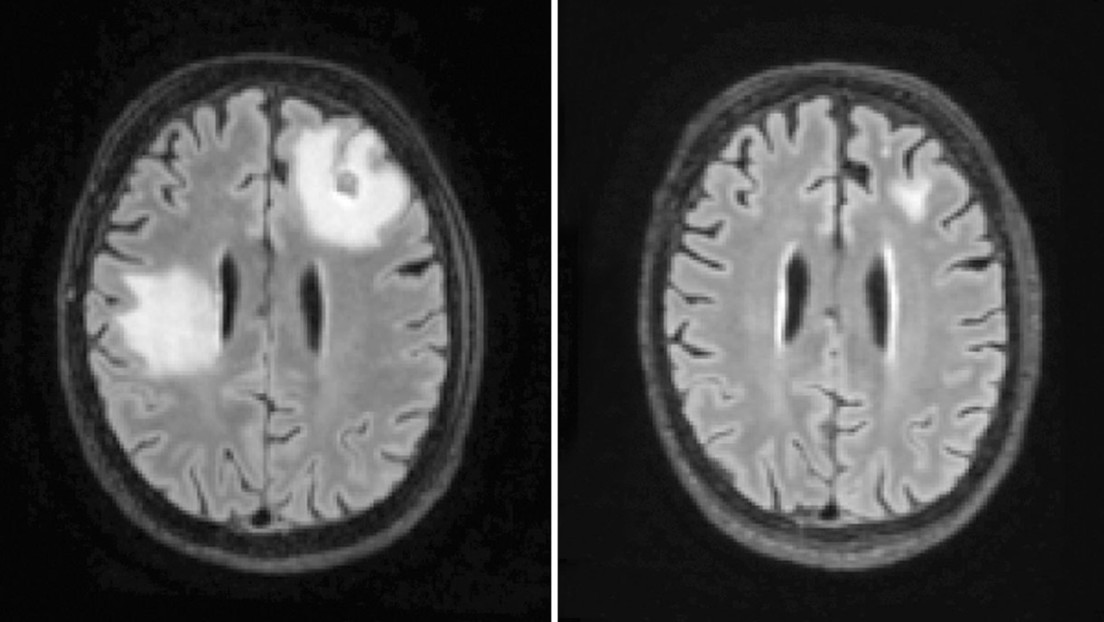

Un absceso cerebral es una acumulación de pus y material infectado en el tejido del cerebro. Pueden causar convulsiones, trastornos visuales o cambios en la visión, el habla, la coordinación o el equilibrio. Su tratamiento a menudo incluye procedimientos quirúrgicos.

Los menores fueron hospitalizados durante unas dos semanas en promedio y más del 80% necesitaron de cirugía cerebral. Ninguno murió a causa de la infección.